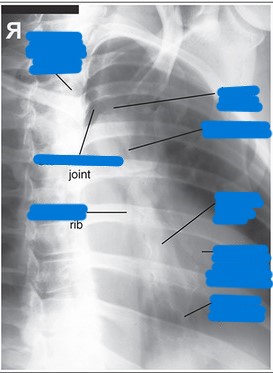

What needs to be demonstrated on an RAO sternum image (film eval)?

slight oblique of sternum utilizing heart shadow

any fractures or inflammatory processes

collimation side to side

marker (L because the right side of the body is not even on the image)

oriented as if person is standing in front of you

What needs to be demonstrated on a lateral sternum image (film eval)?

lateral view of entire sternum

any fractures or inflammatory processes

marker placed anterior for side down (usually L)

collimation anterior to posterior

oriented how you took the image